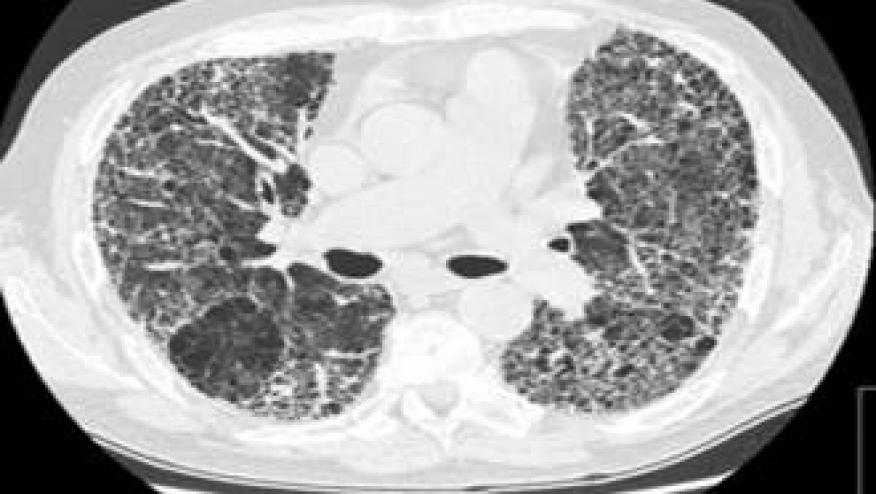

HRCT has emerged as the definitive gold standard in identifying and assessing ILD in CTD patients, offering several critical advantages, including Superior sensitivity, Early detection, Pattern recognition, and disease monitoring. HRCT distinguishes specific morphological patterns that correlate with prognosis and treatment response

Their analysis revealed distinct patterns across CTD-ILD cases:

- Non-specific interstitial pneumonia (NSIP): 36.5% (most common overall)

- Definite usual interstitial pneumonia (UIP): 24.8%

- Organizing pneumonia (OP): 9.8%

- Probable UIP: 3.48%

- Indeterminate UIP: 4.78%

- Lymphoid interstitial pneumonia (LIP): 1.25%

- Other patterns: 19.41%

When analyzing according to disease, specific patterns were identified:

- Systemic Sclerosis (SSc) - NSIP predominates (45-50% of cases)

- Characterized by ground-glass opacities, reticular changes, and lower lobe predominance